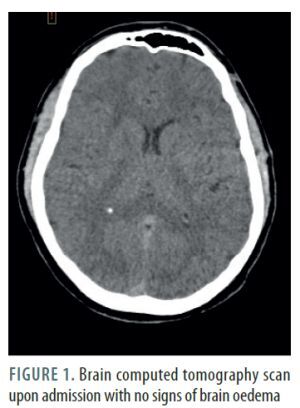

A 24-year-old male patient was admitted to a trauma centre after a motorcycle accident involving a collision with a traffic sign, resulting in a right shoulder injury. Initial evaluation by emergency services showed only paralysis of the right arm; the patient was fully conscious. Upon admission, a whole-body computed tomography (CT) scan was performed, revealing a single fracture of the right collarbone, with no signs of brain injury (Figure 1). Two hours later, the patient fell into a coma, necessitating intubation, sedation, and transfer to the intensive care unit (ICU). A subsequent brain CT scan showed diffuse brain oedema (Figure 2). Intracranial pressure (ICP) was measured at –5 mmHg in the drainage position with the upper body elevated to 30° using a multimodal intracranial probe. The patient remained sedated and ventilated for 48 hours, sustaining stable low ICP levels between –5 and 2 mmHg. Upon cessation of sedation, the patient showed a gradual improvement in consciousness, which was consistent with the changes in ICP levels. Interestingly, higher ICP levels were associated with a better state of consciousness.

FIGURE 2

Brain computed tomography scan after intubating the patient in a coma with signs of diffuse brain oedema